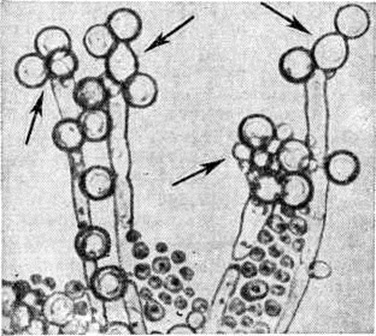

КандидозКандидоз (candidosis; синонимы: кандидамикоз, поверхностный бластомикоз, соормикоз, candidiasis, moniliasis, oidiomycosis) — инфекционное заболевание кожи, слизистых оболочек и внутренних органов, вызываемое дрожжеподобными грибками (грибы рода Candida). Заболевание впервые описано Б. Лангенбеком в 1839 год, хотя оно было известно со времён Гиппократа под названием stomata aphtoides и aphta infantis (Кандидоз Гален). В 1848 год Берг (F. Th. Berg) впервые установил наличие дрожжеподобных грибков в тканях больного человека. Беркхаут (М. Berkhaut) в 1923 год среди дрожжеподобных грибков выделила род Candida. Термин Candida был принят в 1939 год III Международным конгрессом микробиологов. Кандидоз встречается во всех странах мира, особенно часто в поясе тропического и субтропического климата. Число больных различными клинический, формами Кандидоз, особенно висцеральными, имеет некоторую тенденцию к росту. ЭтиологияВозбудителем Кандидоз наиболее часто является Candida albicans, реже С. tropicalis, С. krusei, С. pseudotropicalis, С. stellatoidea и некоторые другие виды. Род Candida (класс Fungi imperfecti) включает св. 80 видов, характеризующихся круглыми, овоидными, реже цилиндрическими, а иногда неправильной формы клетками. Молодые клетки — в диаметре от 2 до 5 микрометров, зрелые — несколько больше. Истинного мицелия дрожжеподобные грибки не имеют; они образуют цепочки (псевдомицелий) из удлинённых клеток, которые соприкасаются друг с другом узким основанием (так называемый перетяжки), длина псевдомицелия до 12—16 микрометров Клетки размножаются прорастанием и многополюсным почкованием (2—3 и более дочерних почек). С. albicans и С. stellatoidea образуют на концах псевдомицелия споры с плотной, обычно двойной клеточной стенкой — хламидоспоры (рисунок 1). Кандида — аэробы; они часто являются сапрофитами слизистых оболочек рта, кишечника, влагалища, кожи. Встречаются в почве, на фруктах и овощах. Для питания они используют из азотистых веществ белки, пептоны и аминокислоты. Кандида считаются условно патогенными микроорганизмами; их патогенность для человека и животных в значительной степени зависит от состояния макроорганизма (смотри полный свод знаний ниже). Наиболее распространенными для выращивания кандида (оптимальная температура 30—37°) являются жидкая среда Сабуро, пивное сусло, мясопептонный глюкозный агар. Для выявления хламидоспор наиболее пригодны среда Чапека — Докса с добавлением твина-80, картофельный агар с желчью, кукурузный и рисовый агар. Кандида сохраняют свою жизнеспособность в культурах (в высушенном состоянии) в течение нескольких лет, переносят многократное замораживание и оттаивание в воде и почве. Они выдерживают конкуренцию со многими микроорганизмами по длительности существования на различных продуктах, например, в кислом молоке, квашеной капусте, фруктовых соках и другие. В культурах и патологический материале грибки погибают при кипячении в течение нескольких минут. Губительное действие оказывают 2—5% растворы фенола и формалина, хлорамина, лизола, йодиды, бораты, сульфат меди и цинка, перманганат калия и другие химический вещества; фунгицидно действуют растворы анилиновых красителей (генцианвиолет, малахитовый зелёный, метиленовый синий и другие). ЭпидемиологияХорошая приспособляемость многих видов рода Candida к окружающей среде обеспечивает им широкое распространение, а также носительство человеком и животными. Например, С. albicans может быть обнаружен на коже, слизистых оболочках и в испражнениях почти у 20% здоровых людей. Кандидоз болеют телята, ягнята, жеребята, домашняя птица и другие; отмечены заболевания и диких животных. Некоторые представители рода Candida ассоциируют с нормальной микрофлорой кожи человека (прежде всего С. albicans). Как источник инфекции наибольшее значение представляют больные свежими формами поражения кожи и слизистых оболочек. |

Кандидоз кожи проявляется в виде подострых дерматитов в складках кожи, изредка с образованием абсцессов и изъязвлением. При гистологический исследовании отмечается межклеточный отёк эпидермиса, паракератоз, акантоз и прорастание нитей грибка в некротизированный эпидермис (рисунок 2). Воспалительная инфильтрация преимущественно из сегментоядерных лейкоцитов наблюдается в основном в дерме. Иногда наблюдается формирование ограниченных абсцессов с наличием распадающихся сегментоядерных лейкоцитов. Впоследствии образуются гранулемы, состоящие из лимфоцитов, эпителиоидных и гигантских клеток (рисунок 3).

Рис. 2. | ||